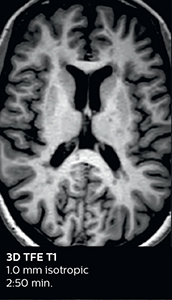

The abbreviated MS protocol for brain is only around 9 minutes, so in case of suspected multiple sclerosis, one or two more advanced sequences may be added, such as PSIR (phase sensitive inversion recovery) or susceptibility-weighted sequences to help us make more confident diagnoses in these inflammatory cases.

In this example, the optional 3D multishot susceptibility weighted sequence with 0.6 mm isotropic voxels is 2 lesions with a central vein sign (arrows) and one lesion with a phase-rim sign (arrowhead). The total scan time, including SmartBrain and axial PD/T2 3mm, is 11:10 min. and is 18:30 min. with the optional 3D PSIR and 3D SWI multishot included.

“We used to have long examination times for certain types of patients, a few lasting more than 40 minutes,” says Dr. Savatovsky. “What is remarkable, is that now all these examinations are below 30 minutes, which opens up opportunity to add more sequences when needed. It’s really hard to keep a patient for more than 40 minutes in the scanner, but because we have now cut scan times by at least 10 minutes, we can add more sequences without making the exam too long. And this is where the new system helps us make a difference. Examples include our examinations for informing brain tumor classification or giant cell arteritis workup, or for intracranial wall imaging – so in patients where we need several advanced sequences or high resolution sequences.” “We added three additional sequences in our brain neoplasm classification exam: a 3D SWI sequence, APT and ASL on top of 3D morphologic sequences, an isotropic DSC (dynamic susceptibility contrast) and multivoxel spectroscopy. I think that in patients that need a classification for brain mass, for example, we can provide a more detailed and confident diagnosis than before, allowing the clinicians to decide for either a medical workup if no tumor is suspected, or for neurosurgery as soon as possible if a neoplasm is suspected.” “In multiple sclerosis patients, we increasingly include a multishot susceptibility sequence [3] in our routine cases, thanks to the shorter scan times. Our abbreviated MS protocol for brain is around 8 to 9 minutes, so we can ask for one or two additional sequences to visualize the central veins, or to get an additional contrast to better depict posterior fossa lesions. In cases of white matter lesions of unknown significance on FLAIR images, for example when we see high signal hyperintensities in the brain, we can add on more advanced sequences such as PSIR (phase sensitive inversion recovery) or susceptibility-weighted sequences to help us in distinguishing between MS and nonspecific or vascular abnormalities in these inflammatory cases.”